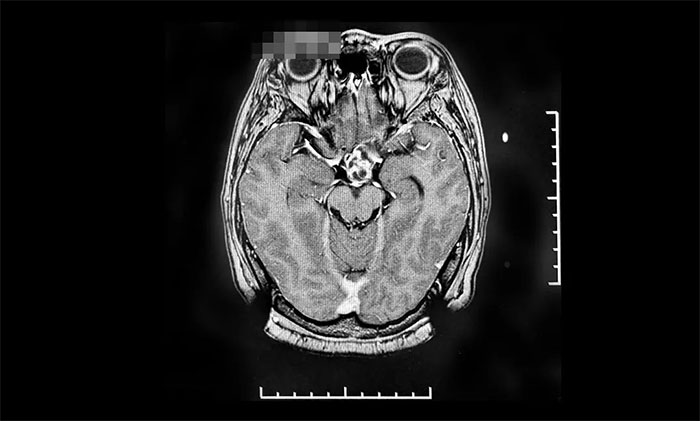

上海蓝十字脑科医院肿瘤科(放疗)头部伽玛刀组陈琦主任团队前期收治了一位颅咽管瘤术后复发患者。该患者为54岁,女性,1996年因双眼视力下降检查发现鞍区占位,于1996年底及2005年两次在外院开颅手术,病理证实为颅咽管瘤。

▲ 肿瘤复发后,来我院行伽玛刀治疗前影像